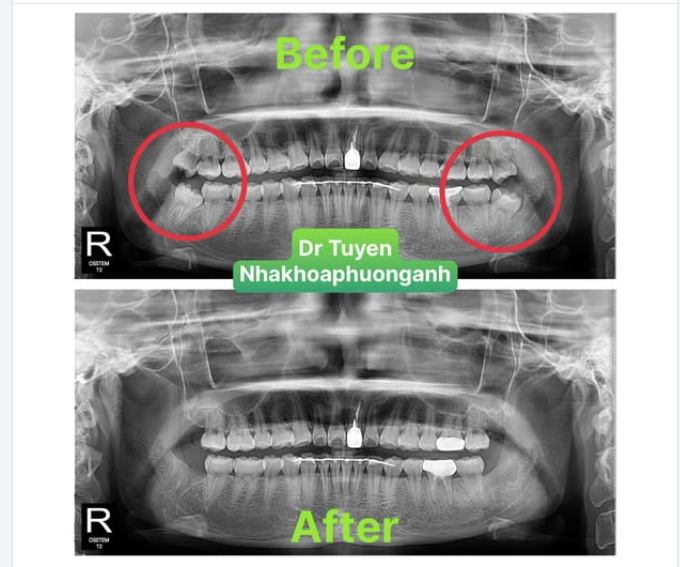

Nhổ răng khôn không đơn thuần là rút chiếc răng ra khỏi xương hàm, mà nó phức tạp hơn, đặc biệt nếu nó bị mọc kẹt.